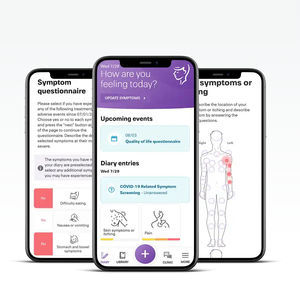

Una solución de gestión de los resultados de los pacientes diseñada para implicar a los pacientes para que participen en su atención médica mediante una notificación y supervisión de síntomas en tiempo real, con procesos clínicos optimizados ...